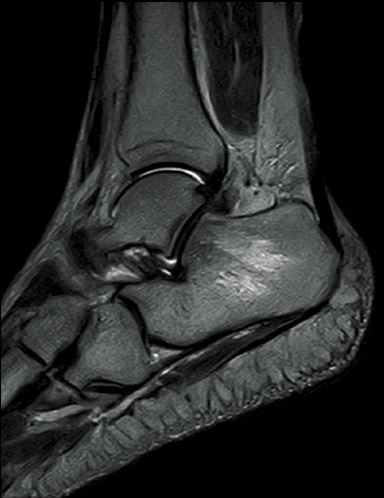

FatSep-T2WI